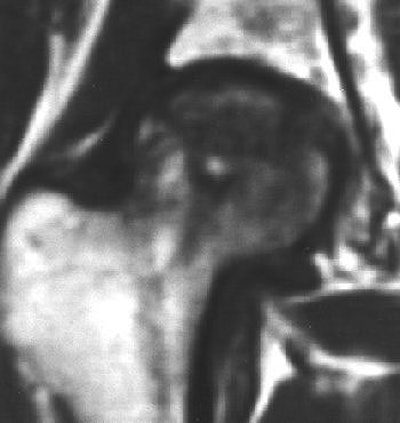

![]() |

| Coronal T1-weighted MR image, obtained six months after A-B and one week after onset of hip pain, shows diffusely decreased signal intensity (D). T1-weighted fat-saturated contrast-enhanced image shows nonenhancing lesion in subchondral area of femoral head surrounded by brightly enhanced marrow in the head and neck (G). Iida S, Harada Y, Shimizu K, Sakamoto M, Ikenoue S, Akita T, Kitahara H, Moriya H, "Correlation Between Bone Marrow Edema and Collapse of the Femoral Head," (AJR 2000, 174: 735-743). |

Iida's group explained that bone marrow edema should be considered a marker for a progressive illness. Its presence can delineate transient osteonecrosis -- a self-limited disease that can be resolved with treatment -- and osteonecrosis, which can progress to destructive arthrosis.